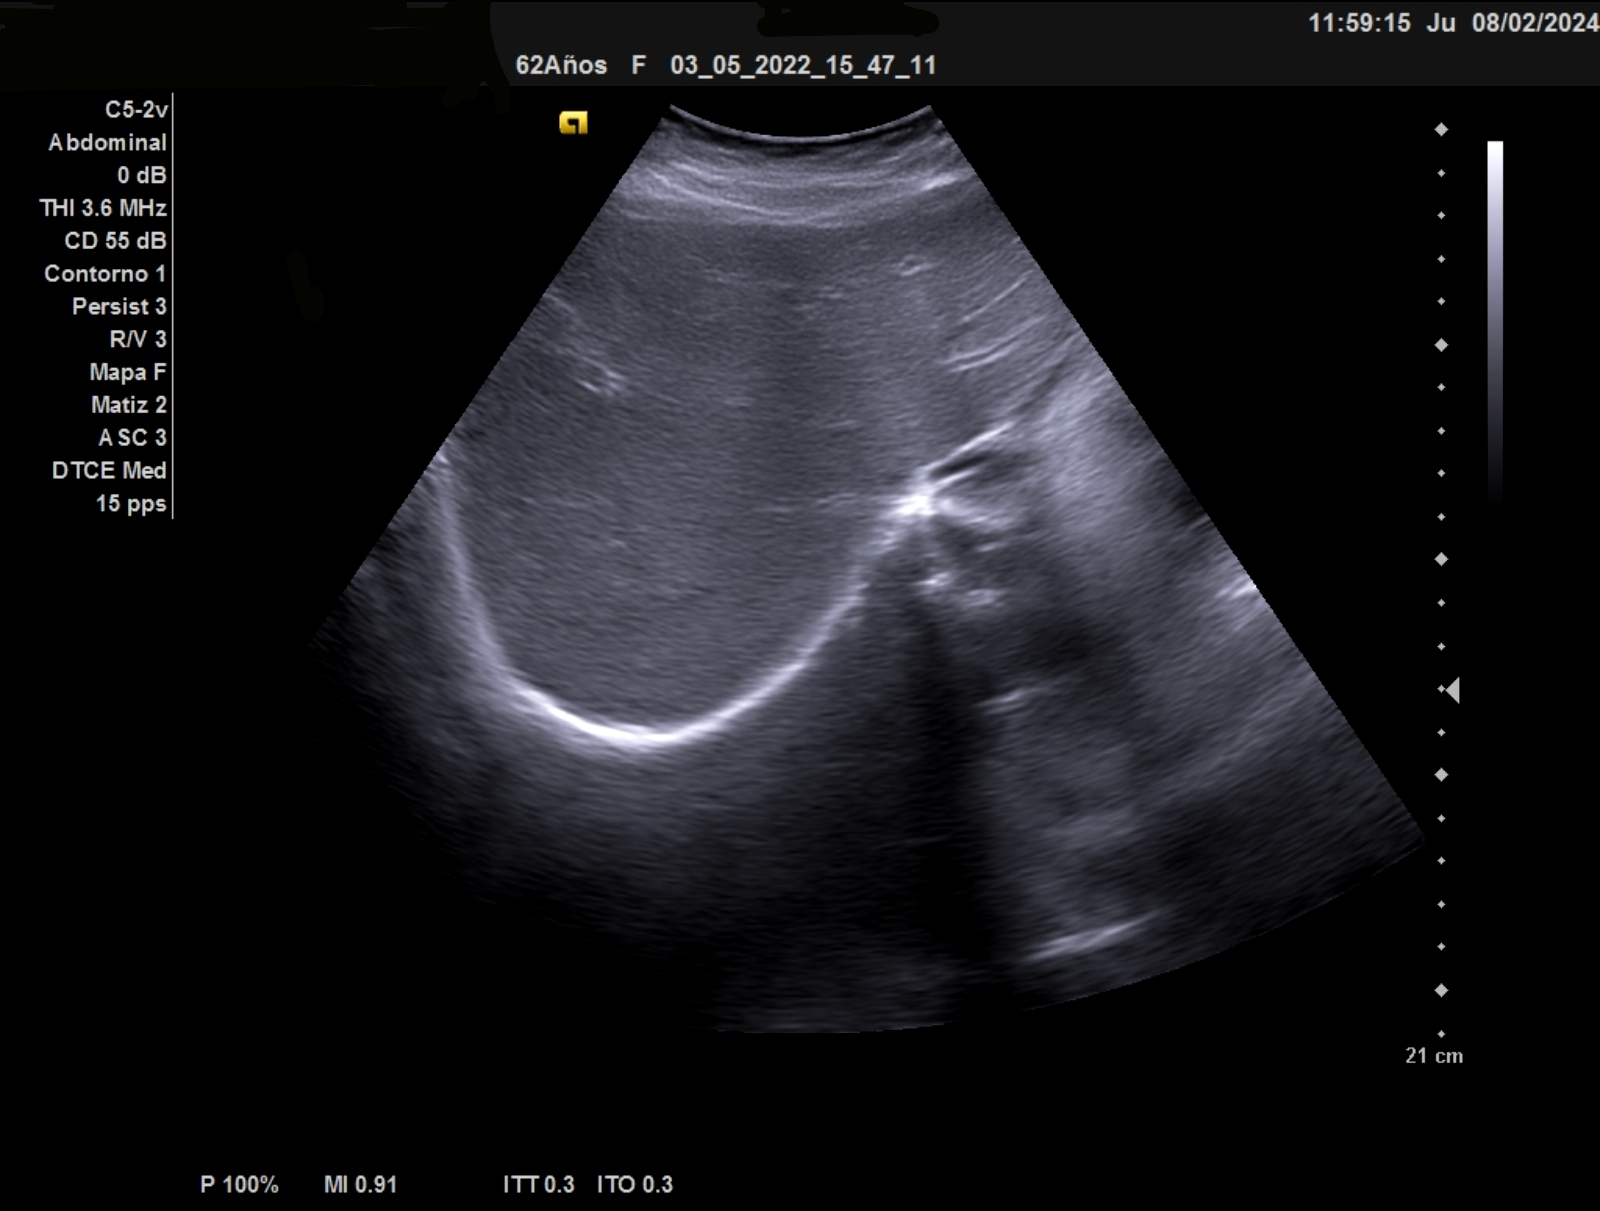

Ecografía clínica: Esplenomegalia con bazo de 12,6 mm eje longitundinal, 9,5 mm transversal y un area 71 cm2 (patológico por encima de 55)

La ecografía clínica debe ser exhaustica, a nivel de hipocondrio izquierdo debe localizarse el bazo con inspección del parénquima, bordes e hilio, debe medirse los 2 diámetros y a eso añadir el area. Se considera patoñogico un diámetro por encima de 12 mm eje longitudinal, >5mm eje transversal y el area por encimad e 55 cm2. En casos de gran esplenomegalia orientará hacia etiología infecciosa: parasitaria, vírica o bacteriana.

Ante la detección de una alteración en el hemograma como la bicitopenia, nos planteamos la ecografía para complementar la ananmesis y la exploración física. La ecografía abdominal debe ser sistemática y exhaustica, inspeccionando las visceras en su totalidad. En el hipocondrio izquierdo puede ser una compleja la visualización completa del bazo. Deben medirse en sus 3 ejes incluyendo el área.